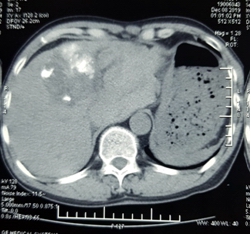

Qua siêu âm, các bác sĩ phát hiện có nhiều máu trong ổ bụng bệnh nhân. Kết quả chụp cắt lớp vi tính cho thấy, khối u gan kích thước hơn 6 cm thâm nhiễm nhu mô gan trái đã vỡ, còn đang có dấu hiệu chảy máu, tạo khối máu tụ lớn khoang hậu cung mạc nối, nhiều dịch máu quanh gan và tiểu khung, chỗ dày nhất 6 cm. Bệnh nhân được chẩn đoán sốc mất máu do u gan vỡ, nguy cơ tử vong cao. Trước tình huống nguy kịch của bệnh nhân, BSCKII.Nguyễn Đình Hướng – Trưởng Khoa Chẩn đoán hình ảnh đã hội chẩn cấp cứu và quyết định thực hiện kỹ thuật nút tắc động mạch gan để cầm máu u gan vỡ trên hệ thống máy chụp mạch số hóa xóa nền (DSA). Các bác sĩ khoa Chẩn đoán hình ảnh, Phẫu thuật – Gây mê Hồi sức đã khẩn trương sắp xếp hệ thống và tiến hành thủ thuật nhanh nhất có thể để “chạy đua” với “tử thần”.

Ảnh 1: Hình ảnh khối u gan hạ phân thùy IV bị vỡ gây khối máu tụ lớn quanh gan trái